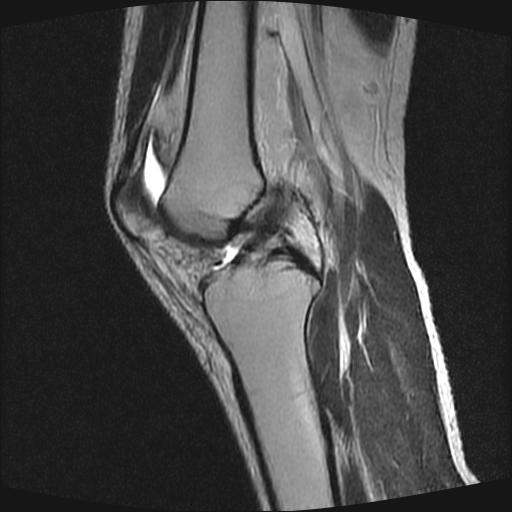

40岁男性,右膝关节外伤,x光平片示,髁间隆突撕脱骨折。

1、前交叉韧带撕裂;

2、外侧半月板后角撕裂;

3、关节腔积液。

前交叉韧带撕裂,关节腔积液.

半月板1-2级损伤   前交叉韧带撕裂伤   关节腔少量积液  诸骨未见新鲜外伤性改变

髁间隆突撕脱骨折;内侧副韧带损伤。

内侧副韧带撕裂及关节腔积液是肯定的,但是前交叉撕裂确定吗?会不会有容积效应的因素,因为前一张前交叉显示清楚,连续性良好,且较光滑。请问楼主有关节镜支持吗?我们医院也经常有这样的患者,但苦于没有关节镜,而无法对照、证实(除非完全断裂),出现了不同的诊断结果只能毫无意义的争论。

1、前交叉韧、内侧副韧带撕裂;

3、关节腔积液。4、髁间脊撕脱骨折。

除了关节积液外并无韧带撕裂,acl胫侧附着点有2束,正常情况下脂肪信号。此病例应加做压脂像以便观察是否有骨损伤。